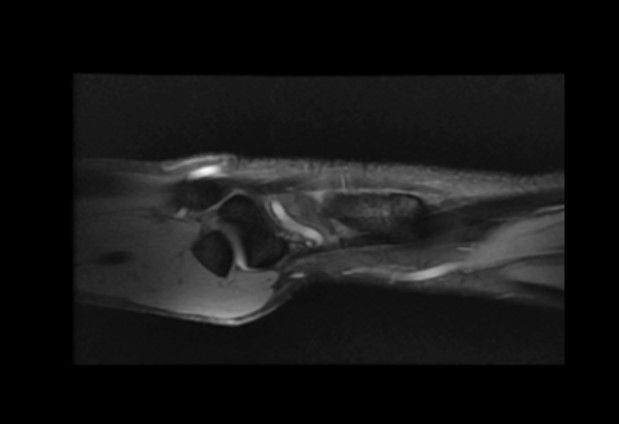

Case 22 - Scaphoid Pseudoarthrosis 57 yr, male, right dominantLeft distal radius fracture 6 years agoLeft wrist ulnar side pain, DRUJ tenderness on dorsal side, ulnar head prominent on volar side, piano key sign: (+)Palmaris longus (+)